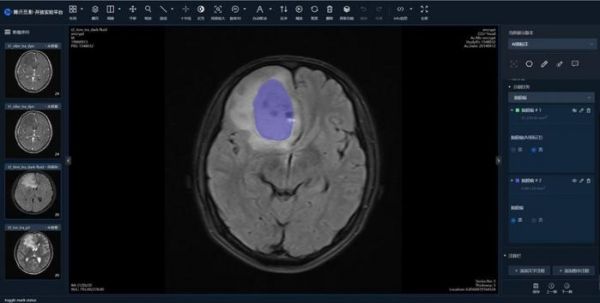

通过平台可标注脑膜瘤磁共振图像等10种疾病医学影像。依托开放平台,腾讯自研医疗影像AI模型6个,包括脑出血原因、肝脏和肝癌分割、眼底多结构分割、脑胶质瘤分割、肺结节检测、青光眼样眼底表现分析,模型涵盖了临床诊断和临床科研等多个应用场景。

据介绍,平台通过云端开放医学影像AI的共性技术,实现了“有网即用”,已累计为超过4000个科研单位和用户提供服务,标注医学影像数据超过7万例。当前,平台可标注包括眼底病变眼底照片、各年龄段磁共振脑影像、脑胶质瘤磁共振图像、肿瘤代谢PET-CT图像、脑膜瘤磁共振图像、宫颈癌磁共振图像等10种疾病医学影像。